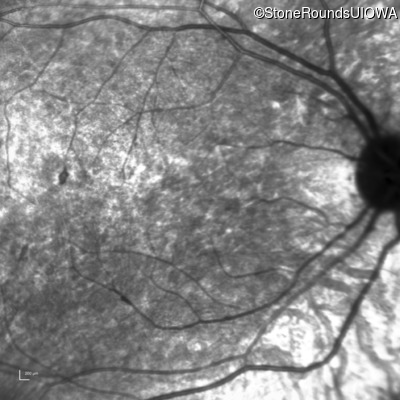

AR Stargardt Disease (IIA)

Age at visit: 8 years

This 8 year old girl had normal vision until age 6 when she failed a school vision screening. That year, she was able to play softball well, but this year she often loses sight of the ball and is often hit by it.

Diagnosis & molecular findings

Disease Gene Allele 1 variant(s) Allele 2 variant(s) Inheritance mode

AR Stargardt Disease ABCA4 IVS38-10T>C IVS38-10T>C AR